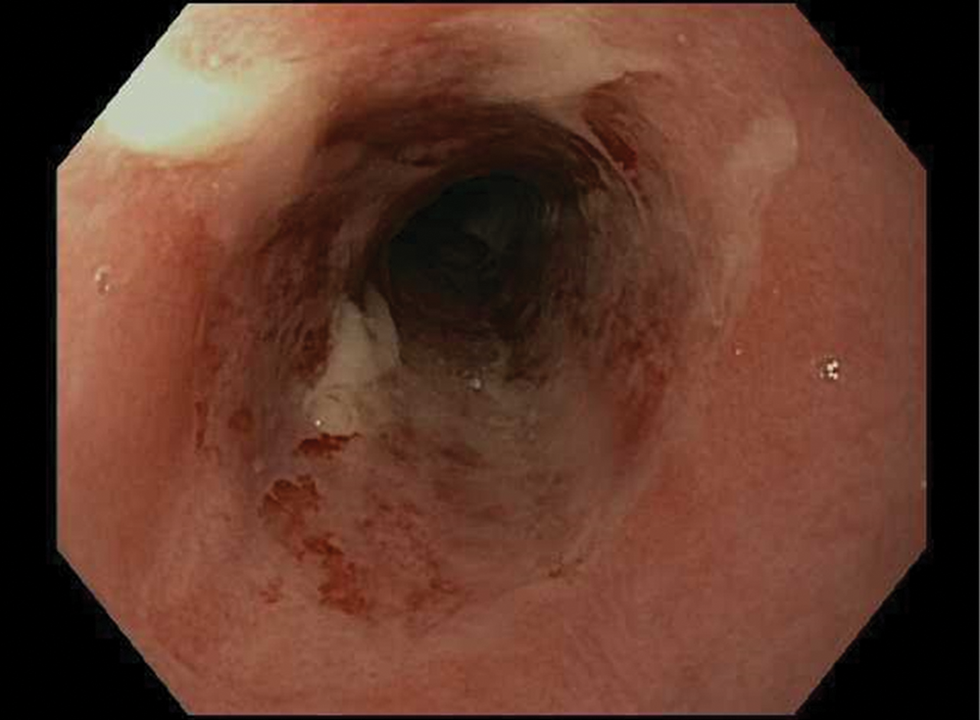

Infectious Diseases of the Esophagus

- Newer drugs such as isavuconazole offer alternatives for treatment of esophageal candidiasis.

- CMV esophagitis remains uncommon in immunocompetent hosts, and is a pathologic finding.

- HSV esophagitis often resolves spontaneously in immunocompetent hosts.

- The involvement of an infectious disease specialist is suggested in complicated cases.

- A new diagnosis of infectious esophagitis should trigger evaluation for HIV, malignancy, or other causes of immunosuppression.